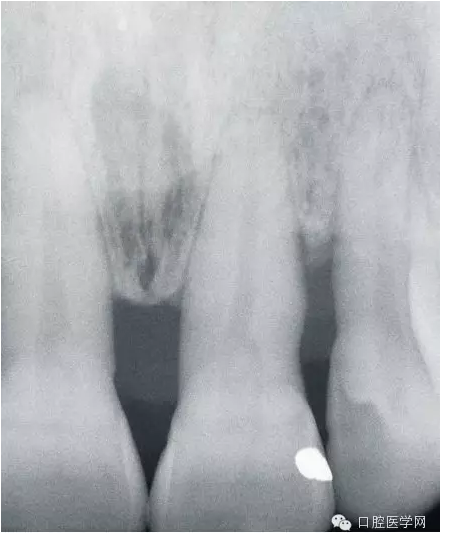

接上面的照片發(fā)一張X-RAY,從圖片中大家應(yīng)該能看到,骨已經(jīng)吸收了,所以骨喪失是牙齦乳頭吸收最主要的原因——牙周區(qū)的紅色美感是依靠骨來支持。

但是,并不是所有的牙齦退縮都是無法在恢復(fù)的。一些患者在去除刺激物包括炎癥,骨是可以基本恢復(fù)原來的健康的(或者說恢復(fù)一些)。當(dāng)然你要通過X-RAY分辨出骨的吸收情況是什么樣。如果象上面第一個(gè)病例那張X-RAY那樣,水平吸收嚴(yán)重就別想了。但如果是下圖這樣,牙齒周圍還保留有骨壁,只要去除炎癥、不良修復(fù)體和調(diào)整咬合情況,骨是可以恢復(fù)的。所以,齦乳頭黑三角最好拍張X-RAY去看看骨的情況,而醫(yī)生不只是對(duì)牙周,同時(shí)對(duì)其他學(xué)科也應(yīng)該有些了解。